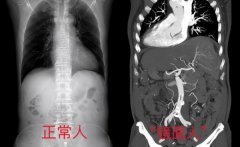

• 七旬大爷脏器全都长反了,肝脏上有个巨大肿瘤!医护团队5小时反向“拆弹”